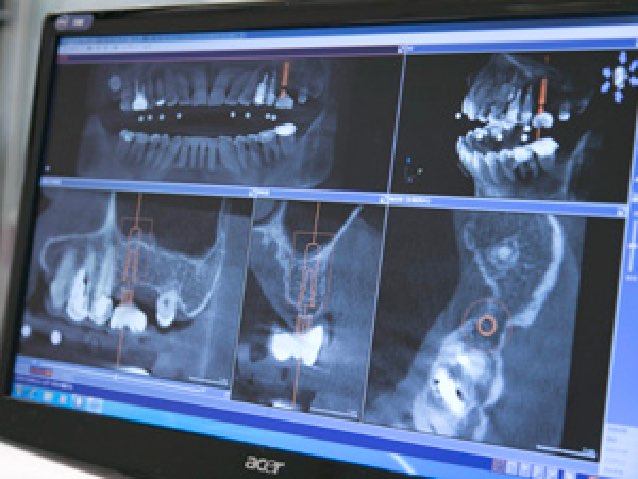

一般的には一人の歯科医師がCTやレントゲンを見て状態を診断を行います。

もちろん一人でも正確に診断することは可能ですが、複数で診断することで幅広い角度から診断でき、より適切な治療を提案できます。

当院のCT診断は、インプラント専門医と歯科放射線学会指導医の二人で行います。

日本歯科放射線学会指導医とは、日本歯科放射線学会が制定した専門資格の一つです。

いくつかの資格がありますが、その中でも指導医はクラスの資格で認定医を指導する立場にあり、全国でも限られた歯科医師のみが有する、希少性の高い専門資格だと言えます。

当院の放射線の指導医は、東京医科歯科大学で准教授として指導しています。